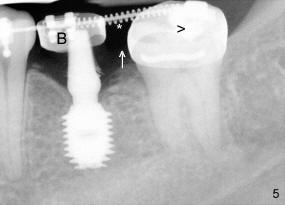

The tooth #19 has been lost for 8 years with tilting of #18 (black line in Fig.1). A 6x8 mm Bicon implant (3 mm post) was placed as distal as possible (I in Fig.2). Three months later, the implant was uncovered with evidence of osteointegration (arrowheads in Fig.3). A 4x6.5 mm 0 degree non-shouldered abutment with 3 mm post (A) was inserted into the implant well. The flat surface of the abutment needed to face distal in order to seat the abutment without interference. The implant/abutment complex was used as an anchorage to upright #18. The tooth #17 was extracted prior to orthodontic treatment (compare Fig.5,6 vs. 1-3). A bracket was bonded to Jet temporary crown of #19 and open coil spring was placed between #18 and 19. In the first two months, distalization of #18 is limited (between black and white lines in Fig.4), partially due to the fact that the bracket of #19 was debonded quite easily. A premolar band (B in Fig.5) was cemented to the temporary crown of #19. In another two months, the tooth #18 was pushed to desired position (arrowhead) under the tension of open coil spring (*). The mesial crest height of #18 was increased during uprighting (arrow, as compared to Fig.1-3). A new temporary crown was fabricated to fit the enlarged space of #19 with cementation of a molar band. The next problem is that the new molar temporary crown was easily dislodged from the 4x6.5 mm abutment even with a permanent cement. A larger abutment (5x6.5 mm) was used (Fig.6), with relining the temporary crown. The upper end of the larger abutment has sharp edge (Fig.8: white arrowhead, as compared to rounded edge of the smaller abutment (Fig.7). This may also contribute to better retention. In another 3 months, the temporary crown was dislodged again. An even larger abutment (6.5x6.5 mm with two flat surfaces (blue arrowheads in Fig.9) was adopted.